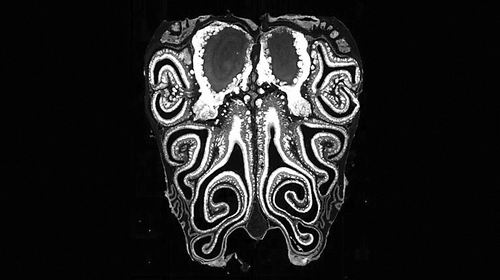

图片来源:Datta Lab

小鼠鼻腔的显微镜横截面图像,显示了鼻腔上皮的解剖结构。

本报讯 研究人员以前所未有的细节绘制了小鼠鼻腔中的嗅觉受体分布图谱。这一成果颠覆了人们对鼻子如何产生嗅觉的认知。

在研究中,科学家对来自数百只小鼠的约500万个神经元进行了检测。他们首先通过单细胞测序确定了由鼻腔神经元表达的嗅觉受体,然后利用空间转录组学绘制了关键基因的表达位置图谱。研究人员由此确定了这些受体的位置,并证明它们总是以从鼻腔顶部延伸至底部的水平条纹形式排列。

“每个受体在鼻腔中都占据一个特定的位置。鼻腔中有上千个位置,每个受体基本上都会在一个条带中表达,而这些受体条纹会与其他条纹发生重叠,最终形成上千个相互交错的条纹。”论文共同作者、美国哈佛医学院的Sandeep Robert Datta说。